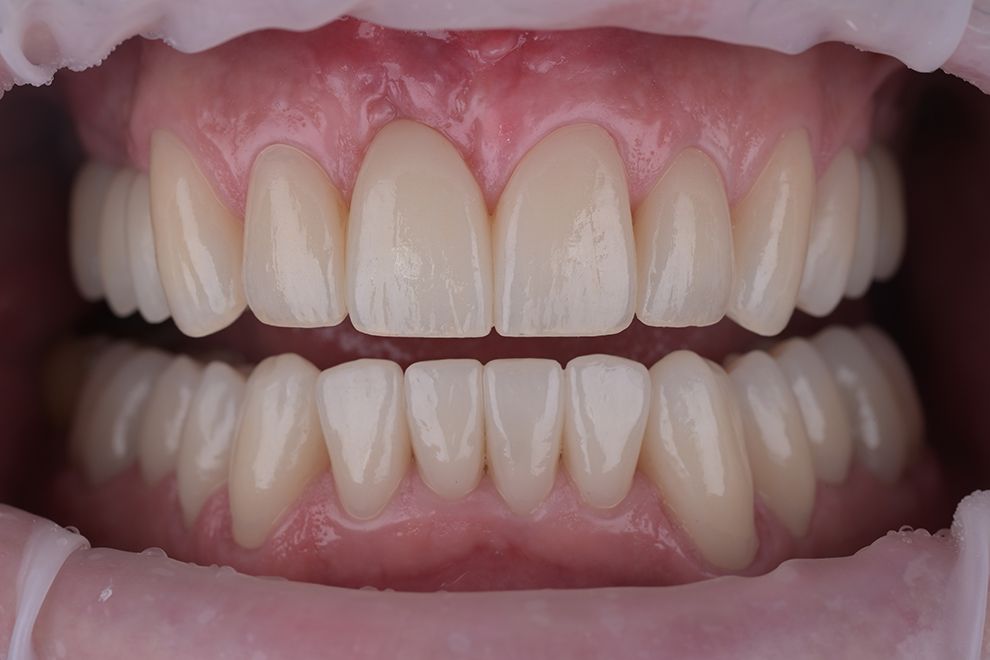

до и после

Хочу выразить огромную благодарность врачу Котоменкову Сергею и его помощнику за профессиональную реставрацию зуба, внимательное отношение и отличную работу!!!